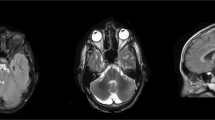

A 34-year-old man from non-consanguineous German parents without family history of ataxia or dementia presented with progressive upper limb hyperkinetic movements starting at age 30 years, subtle and slowly progressive gait disturbance starting at age 33 years, and impaired fine motor skills starting age 34 years. Childhood development had been normal and after finishing high school, he had worked as a medical technician. Upon neurological examination, the patient showed—apart from cerebellar oculomotor disturbances (saccadic smooth pursuit eye movements, hypermetric saccades), truncal (ataxic stance and gait) and appendicular ataxia (limb dysmetria, kinetic tremor)—myoclonic jerks of the upper limbs, and spastic gait disturbance. Chorea, dystonia, parkinsonism, epilepsy, and urinary tract symptoms were absent. Clinical signs of neuropathy were not present, and secondary sexual characteristics were normal. In the consecutive 3 years from first examination, gait and stance became more unstable and upper limb ataxia worsened, as reflected by an increase of 2.5 points on the Scale for the Assessment and Rating of Ataxia (SARA: 15to 17.5 points) [15]. Neuropsychological evaluation including the Test battery for attentional performance (TAP), the Wechsler Memory Scale-Revised (WMS-R) and the Verbal learning and memory test (VLMT) indicated pronounced attention deficits and a decline in memory performance (age and education adjusted scores were lower or far below average). Visuospatial dysfunction, affective and behavioural symptoms were not observed, thus not meeting the full characteristics of the cerebellar cognitive affective syndrome [16], as described for other previous STUB1 patients [4, 6,7,8]. Due to cognitive decline and worsening ataxia, he had to change his workplace within the company and to reduce the workload to part-time. Prolongation of the central motor conduction time to the lower limbs provided corroborative electrophysiological evidence for pyramidal tract damage. Nerve conduction studies revealed—clinically inapparent—axonal motor neuropathy. In addition to severe cerebellar atrophy, MRI brain scan showed T2-weighted hyperintensity in the dentate nuclei and bilateral parietal atrophy (Fig. 1). Whole-exome sequencing of the index patient revealed a previously unreported heterozygous start-lost loss-of-function (LoF) variant c.3G>A in the start codon of STUB1 (NM_005861.4: p.?). This variant is absent in both 13,140 in-house WES/WGS datasets as well as in the 276,000 alleles of gnomAD. Not only all exonic, but also all intronic regions were covered with a coverage of > 20× (except merely a 56 base pair region in intron 1, which was still covered with > 13×) by whole exome sequencing, making it unlikely that a putative second variant in the intronic region of STUB1 (and thus a possible autosomal-recessive mode of inheritance) would have been missed (Fig. 2a). Likewise, WES-based CNV analysis by ClinCNV (https://www.biorxiv.org/content/10.1101/837971v1) did not reveal any CNVs within the chromosomal region 16p13.3. Together with the identification of two SNPs in neighbouring RHBDL1 in a heterozygous state (rs111852492 and rs370469600, located 3369 and 2851 bp upstream of the STUB1 transcript, respectively), these analyses did not provide any evidence that a putative CNV (e.g., a microdeletion) would have been missed. Sanger sequencing confirmed presence of the variant in the index patient, and its absence in the other family members including both parents (Fig. 2b, c), with paternity confirmed by analysis of five short-tandem-repeat (STR) loci in the index patients and both parents, thus demonstrating de novo occurrence of this variant. The absence of the variant not only in the parents, but also in both siblings (Fig. 2b) not only corroborates potential pathogenicity of the variant, but also makes it less likely that a putative mosaicism in the parents might have been overlooked.

Imaging findings of the index patient with the heterozygous de novo STUB1 variant. T2-weighted sagittal (left) and coronal (middle) and T1-weighted axial (right) MRI imaging showing severe cerebellar degeneration (blue arrows), atrophy of the parietal lobes (white arrows) and hyperintensity of both dentate nuclei (dark yellow arrows)

Our findings thus not only provide corroborative genetic and preliminary mechanistic evidence for STUB1-disease as an autosomal-dominant disorder, but also add further phenotypic evidence for the similarity of autosomal-dominant STUB1 disease with its autosomal-recessive counterpart. Autosomal-recessive STUB1-disease has been described to cause an early-onset multisystemic ataxia including cerebellar ataxia, pyramidal tract damage, hyperkinetic movement disorders and cognitive decline as the main affected systems [1, 2]. These systems—as well as the early-onset of the disease—are exactly all mirrored by the case presented here, which presented with cerebellar ataxia, distal myoclonus, spastic gait disorder and cognitive dysfunction (Fig. 3d), and with structural brain damage extending beyond the cerebellum to the cerebral cortex. The presence of bilateral signal alterations of the dentate nuclei along with cerebellar atrophy support the notion of a common neuroradiological feature in SCA48, recently referred to as “crab sign” due to its morphological appearance [18]. Although this striking MRI imaging sign is very rare in hereditary ataxias, systematic imaging studies are warranted to investigate whether it is really fully specific to STUB1-disease.